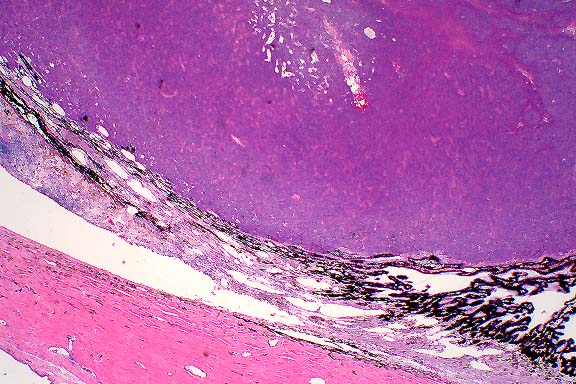

2x

obj

- Case 12-2. Lymph node. Extensive necrosis and inflammation

with focal areas of hemorrhage.

40x

- Case 12-2. Lymph node. Multifocally within zones suppuration

and necrosis, are multiple large colonies of bacteria.

obj, Brown & Brehn

- Case 12-2. Perinodal fat. Brown & Brehn staining

reveals that bacterial colonies are composed of short reddish-blue

(Gram negative) rods.

- AFIP Diagnosis: Lymph node: Lymphadenitis, necrotizing,

suppurative, diffuse, severe, with numerous bacilli, Siberian

polecat x black-footed ferret (Mustela eversmanni x M. nigripes),

mustelid.

-

- Note: Necrosis, suppurative inflammation and hemorrhage

are present within the surrounding perinodal tissues in some

sections.